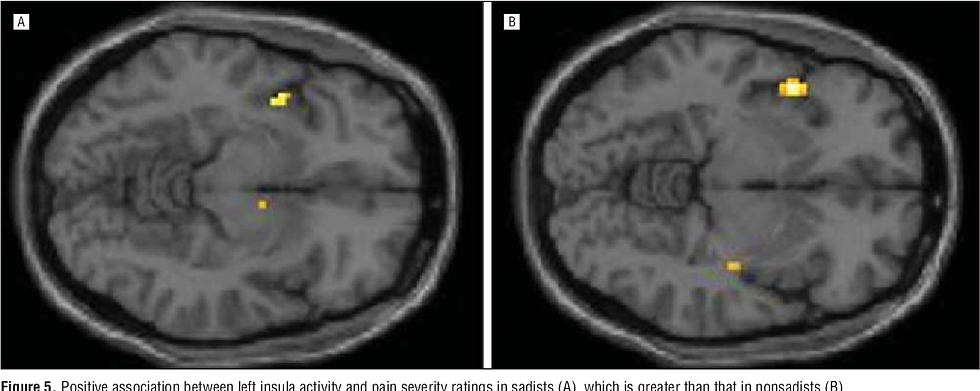

Another relevant factor involves the neural processing of pain and emotions. Neuroimaging studies indicate that sexual sadists exhibit heightened activation in the amygdala and anterior insula when observing others in pain, compared to the control group. These brain regions are involved in emotional processing and interoceptive awareness. This evidence suggests that sadists may experience intensified emotional or arousal responses when witnessing suffering.

Research also shows stronger functional connectivity between the amygdala and anterior insula in sadistic individuals. This means the two brain areas work more closely together, which may help explain how another person’s pain can turn into a feeling of pleasure or power for them.